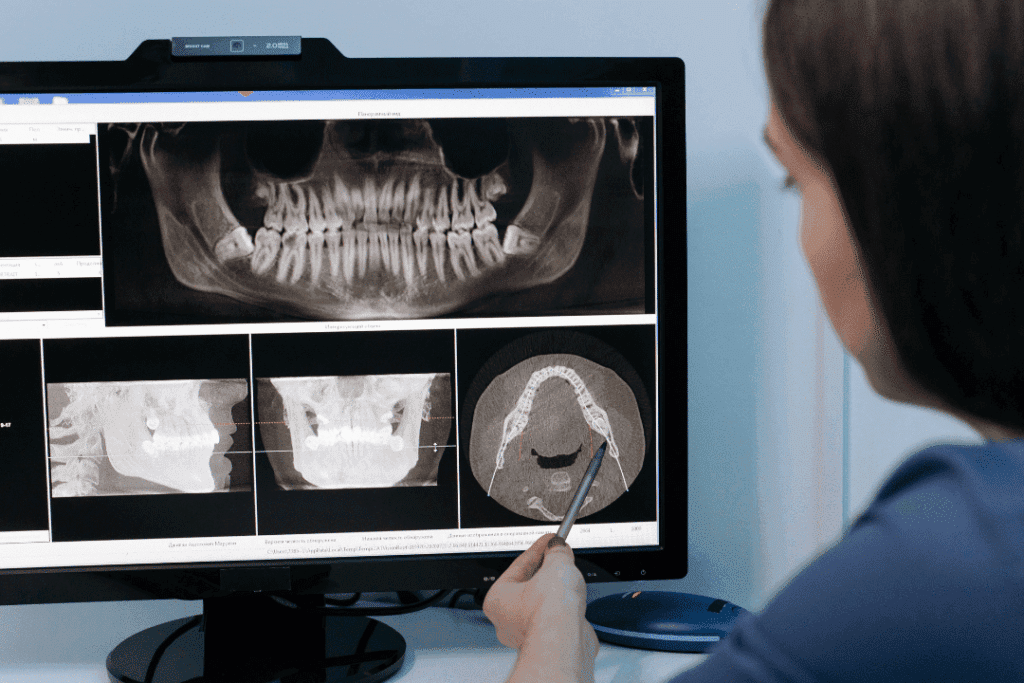

While digital scans capture surface-level details, 3D imaging goes even deeper, offering a full picture of the patient’s bone structure, tooth roots, airway space, and jaw alignment. These tools often cone-beam CT scanners give orthodontists crucial insights into how teeth sit within the jaws and how surrounding structures contribute to alignment issues.

This technology is especially valuable in complex cases, where understanding root position or jaw relationships is essential for safe, effective treatment. With 3D imaging, orthodontists can make decisions that protect long-term oral health, not just aesthetics.

What 3D Imaging Reveals That Traditional X-Rays Cannot

- Root position and angulation

- Jaw joint (TMJ) positioning

- Early signs of impacted teeth

- Airway space and structural narrowing

- Crossbites, underbites, and overbites

- The relationship between upper and lower jaws

This level of detail helps orthodontists make more informed decisions about whether a patient needs braces, aligners, expanders, or other orthodontic tools to achieve an ideal outcome.